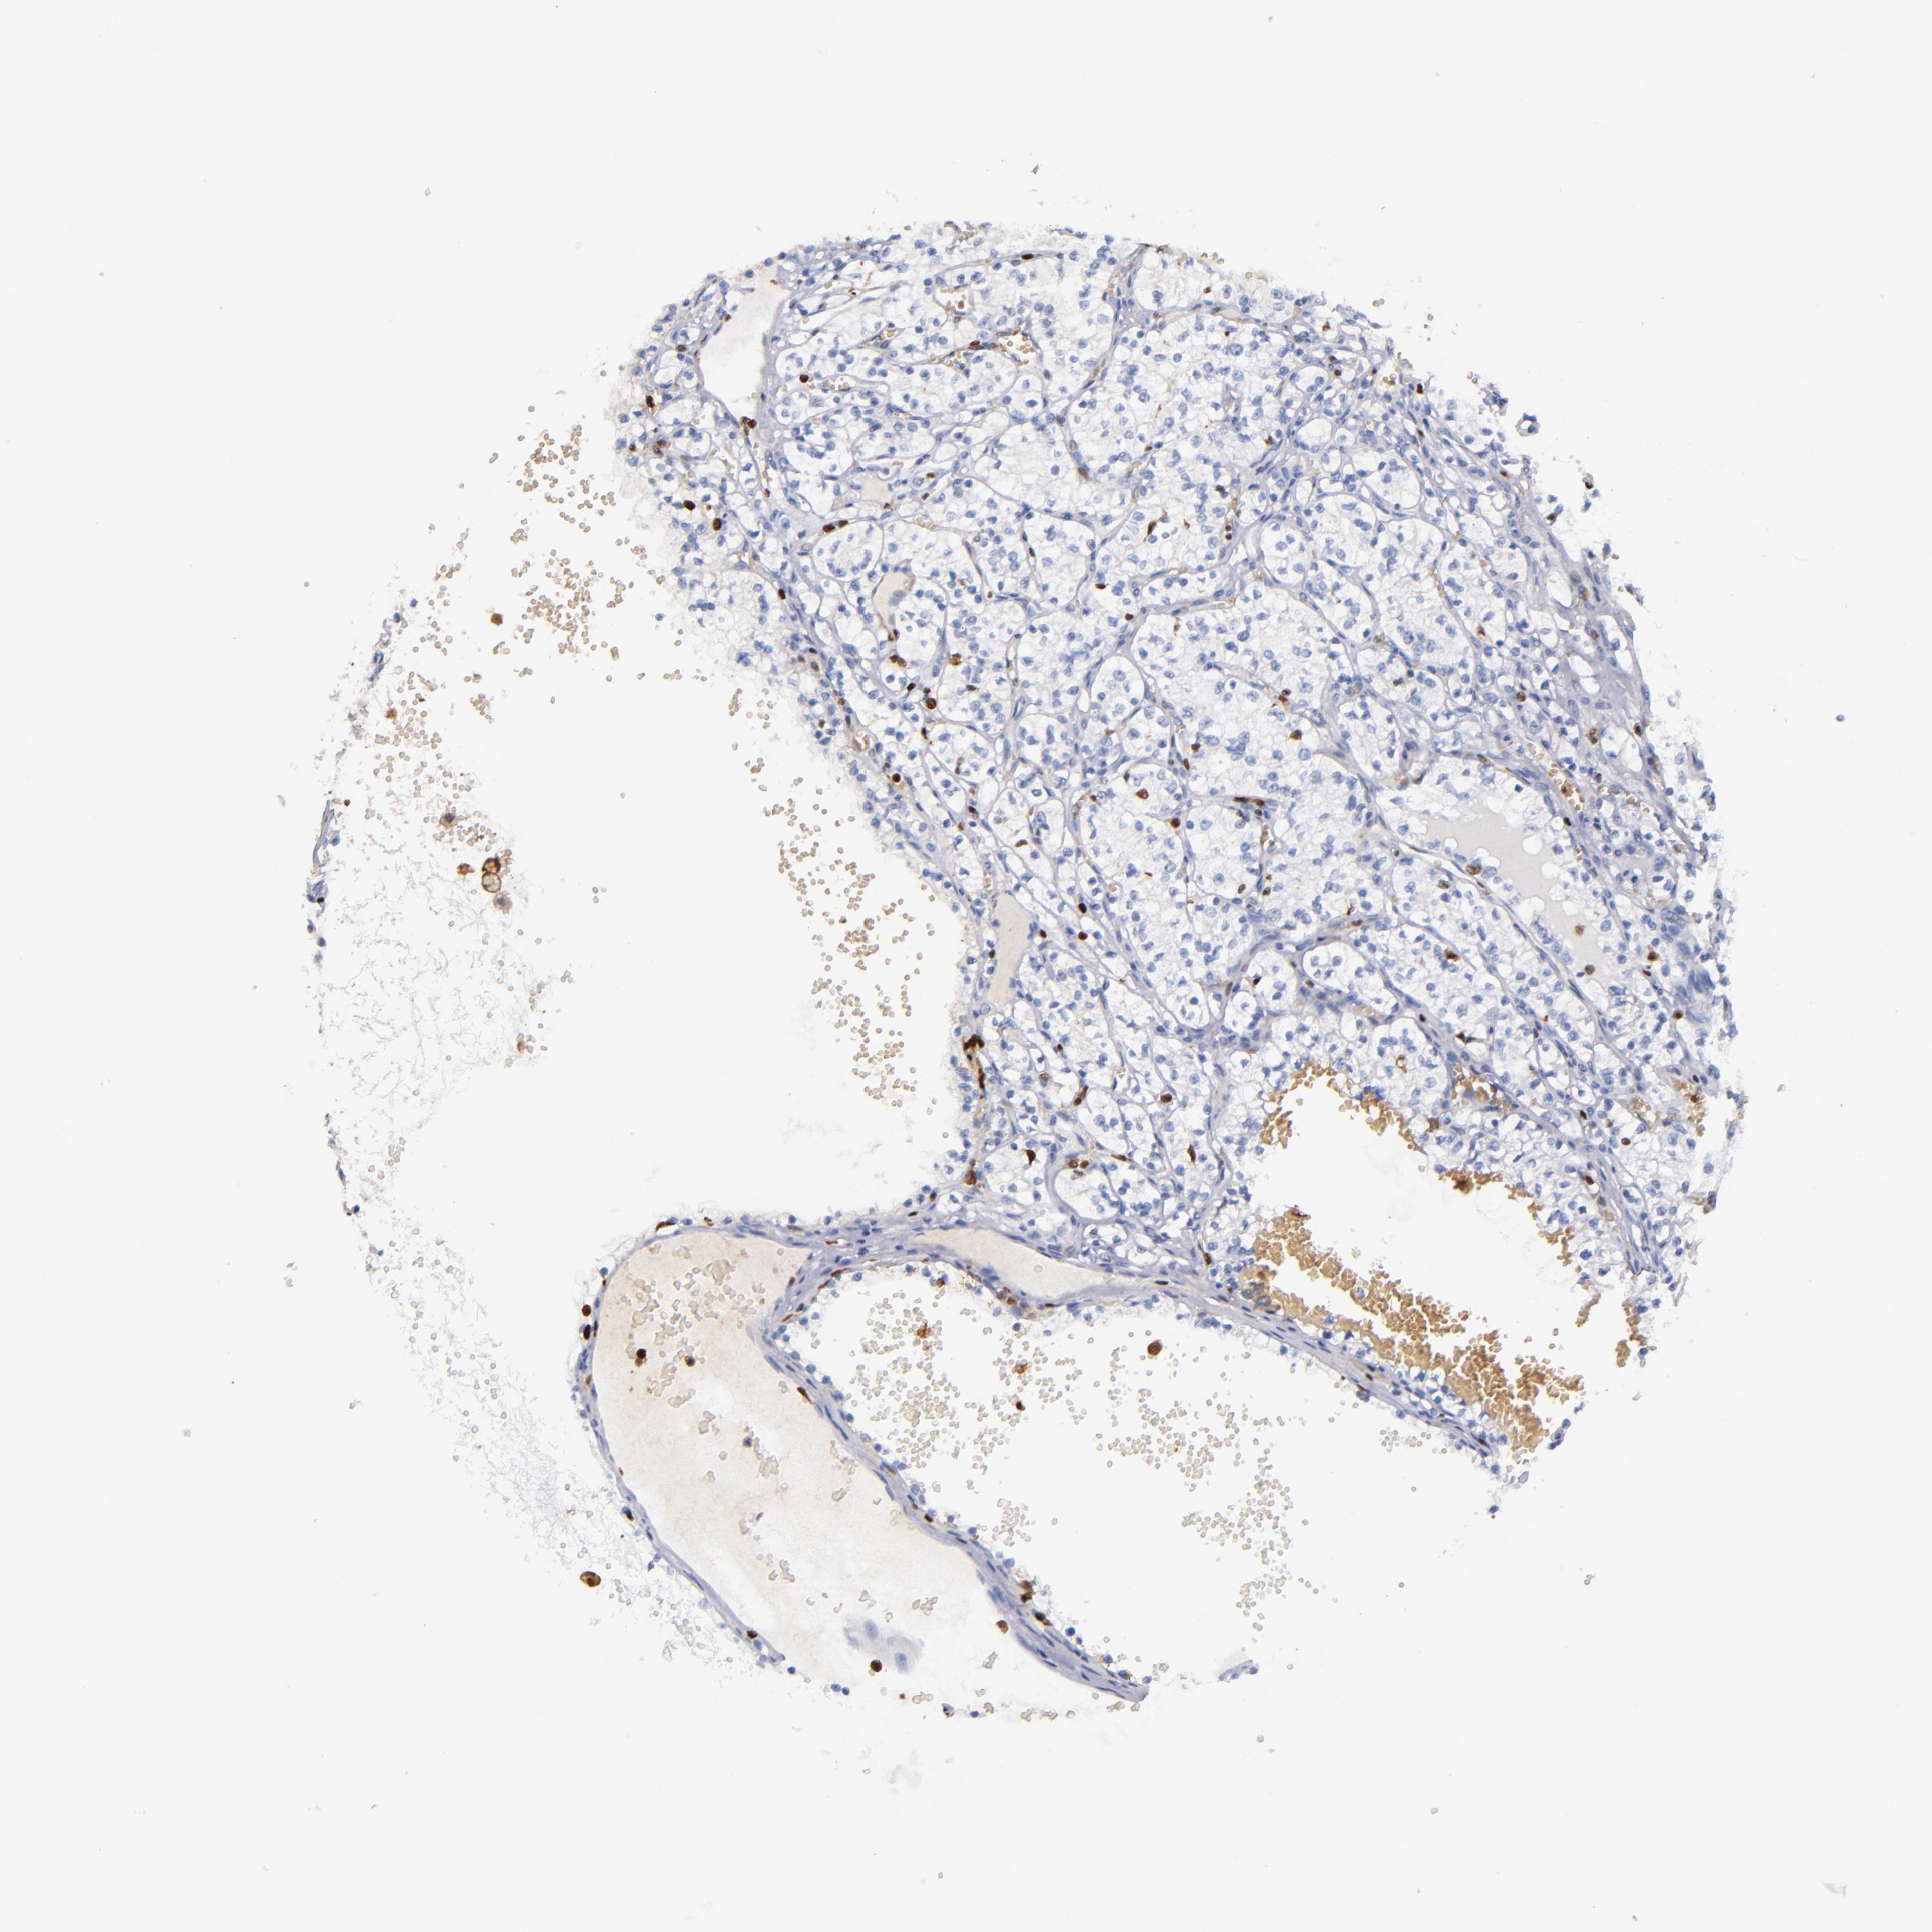

KIDNEY RENAL CLEAR CELL CARCINOMA (VALIDATION) - Interactive survival scatter ploti

The Survival Scatter plot shows the clinical status (i.e. dead or alive) for all individuals in the patient cohort, based on the same data that underlies the corresponding Kaplan-Meier plots. Patients that are alive at last time for follow-up are shown in blue and patients who have died during the study are shown in red.

The x-axis shows the expression levels (FPKM) of the investigated gene in the tumor tissue at the time of diagnosis. The y-axis shows the follow-up time after diagnosis (years). Both axes are complimented with kernel density curves demonstrating the data density over the axes. The top density plot shows the expression levels (FPKM) distribution among dead (red) and alive patients (blue). The right density plot shows the data density of the survived years of dead patients with high and low expression levels respectively, stratified using the cutoff indicated by the vertical dashed line through the Survival Scatter plot. This cutoff is automatically defined based on the FPKM cutoff that minimizes the p-score. The cutoff can be changed by dragging the vertical line or by entering a cutoff value in the square labeled "Current cut-off".

Under the Survival Scatter plot the p-score landscape (black curve; left axis) is shown together with dead median separation (red curve; right axis). Dead median separation is the difference in median mRNA expression between patients who have died with high and low expression, respectively. It is calculated as follows: median FPKM expression of dead patients with high expression - median FPKM expression of dead patients with low expression. This is intended to aid the user in visually exploring custom cutoffs and the associated p-scores and dead median separation.

Individual patient data is displayed and can be filtered by clicking on one or more of the category buttons on the top of the page. Categories describing expression level and patient information include: high, low, alive, dead, female, male and tumor stages. The scale of the x-axis can be toggled between linear and log-scale by clicking on the "x log" button. Mouse-over function shows TCGA ID, patient information and mRNA expression (FPKM) for each patient.

& Survival analysisi

Kaplan-Meier plots summarize results from analysis of correlation between mRNA expression level and patient survival. Patients were divided based on level of expression into one of the two groups "low" (under cut off) or "high" (over cut off). X-axis shows time for survival (years) and y-axis shows the probability of survival, where 1.0 corresponds to 100 percent.

S100A4 is not prognostic in Kidney Renal Clear Cell Carcinoma (validation)

Best expression cut offi

Based on the FPKM value of each gene, patients were classified into two groups and association between prognosis (survival) and gene expression (FPKM) was examined. The best expression cut-off refers the FPKM value that yields maximal difference with regard to survival between the two groups at the lowest log-rank P-value. Best expression cut-off was selected based on survival analysis .

When clicking on this number, the vertical dashed line indicating cut-off, the interactive survival plot, and the Kaplan-Meier curve will be adjusted to show results based on the best expression cut-off.

: 108.1

Average pTPM 173.2

Number of samples 100